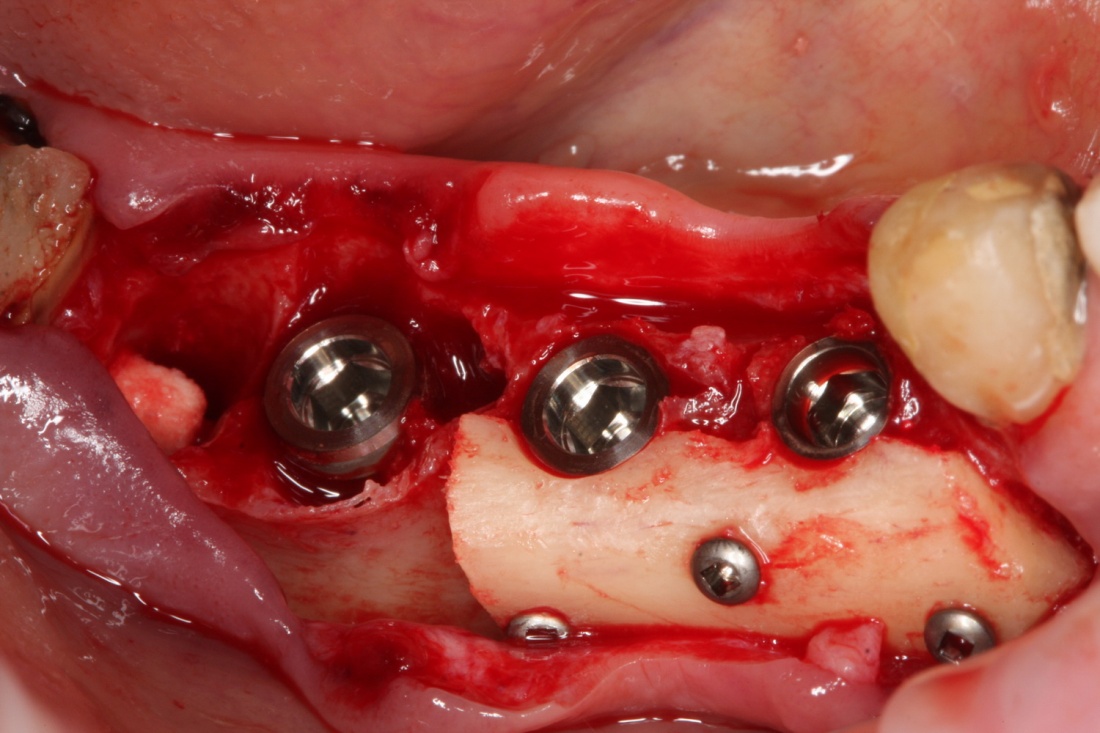

Остеопластика или «наращивание костной ткани» при имплантации — выбор метода и отдаленные результаты.